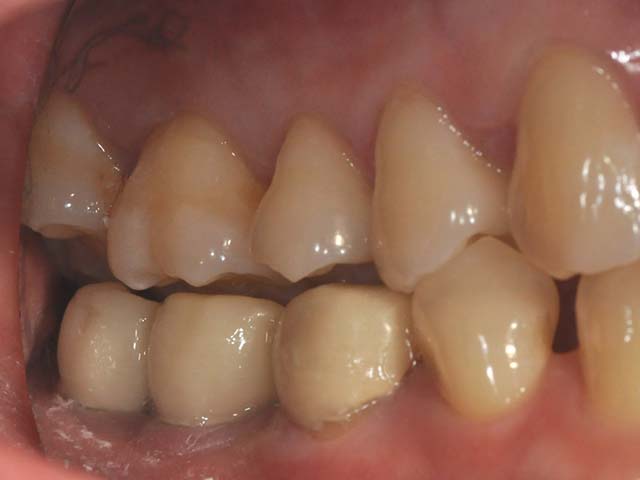

牙橋嚴重蛀牙,即拔即種,避免二次傷口 首頁 案例分享 人工植牙 牙橋嚴重蛀牙,即拔即種,避免二次傷口 多年前製作之牙橋,因為二度齲齒,導致支台齒蛀蝕,而需重新製作 牙橋支臺齒嚴重蛀牙 STEP1.拔除殘根並植入兩根植牙 STEP2.骨粉填補缺損骨頭缺陷 STEP3.三個月後,準備製作正式假牙 STEP4.正式假牙完成